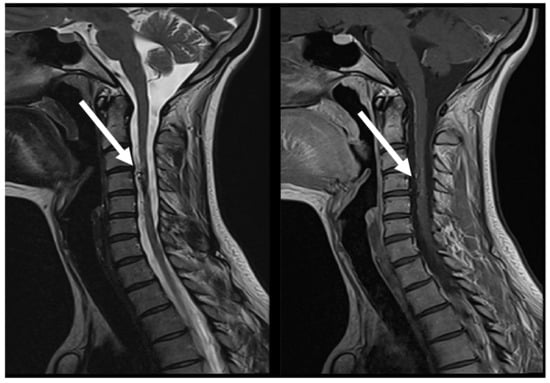

7.2. Second Episode (2020)

7.3. Third Episode (2023)